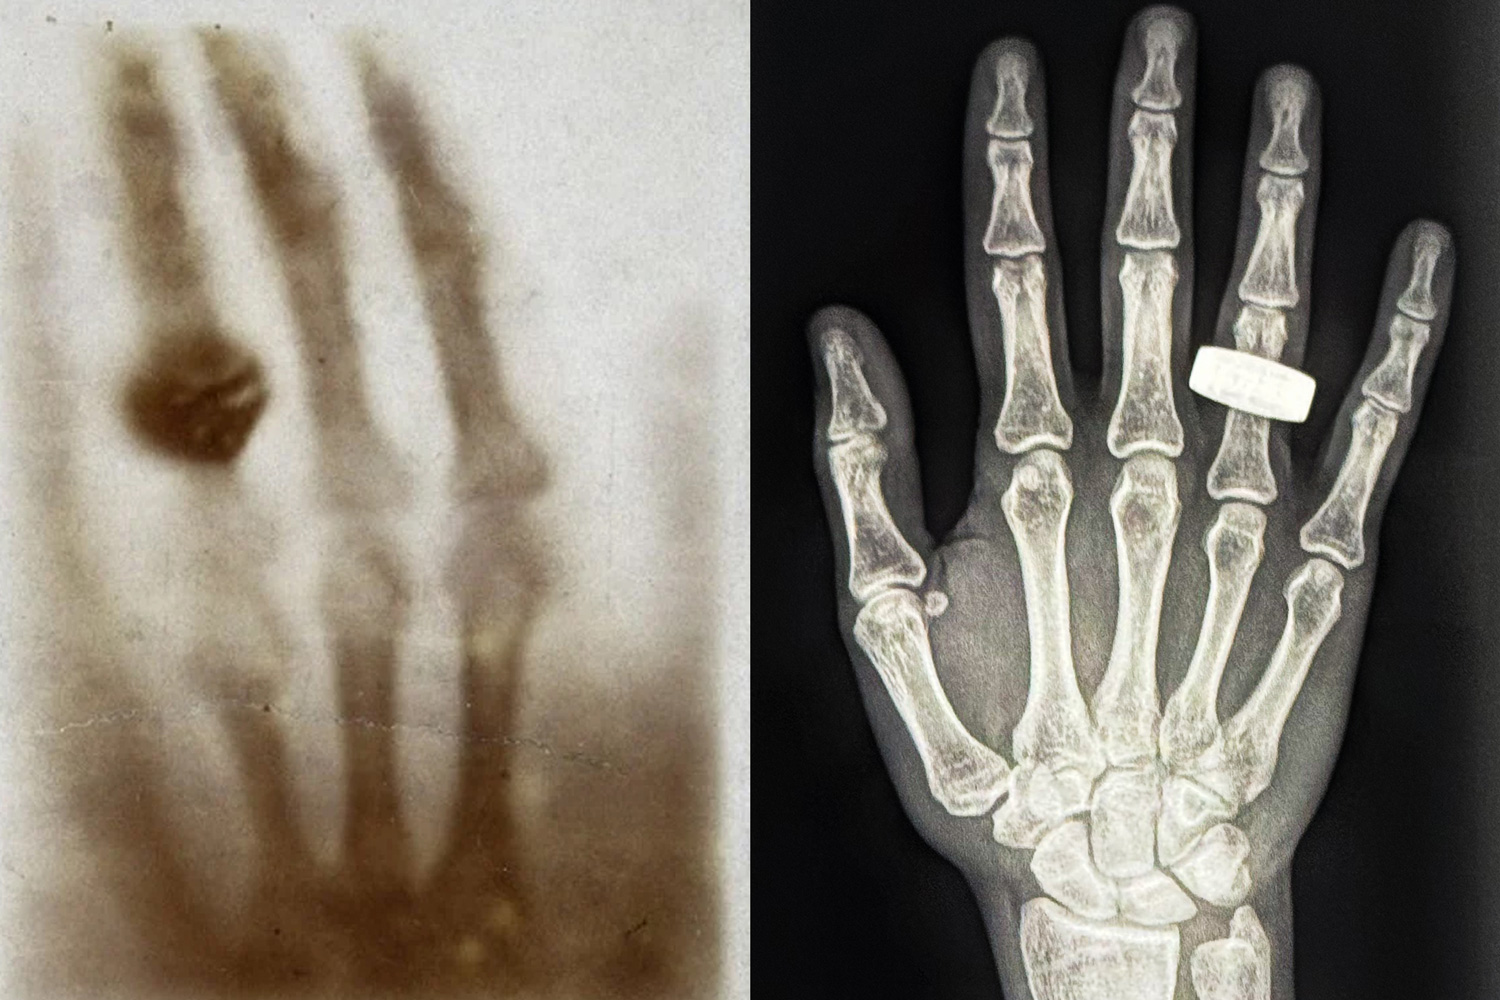

Many of us have gotten an X-ray at one time or another, either at the dentist’s or the doctor’s office. Now, astronauts orbiting Earth have shown it’s possible to take an X-ray in space. The effort will help future space explorers diagnose and monitor medical conditions, from fractures and sprains to signs of bone decalcification, while in orbit.Last week, crew members aboard the Fram2 mission posted to social media and shared the first-ever medical X-ray image taken in space. The image is a black-and-white scan of a hand with a…